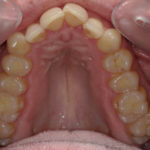

Présentation cas n°1 :